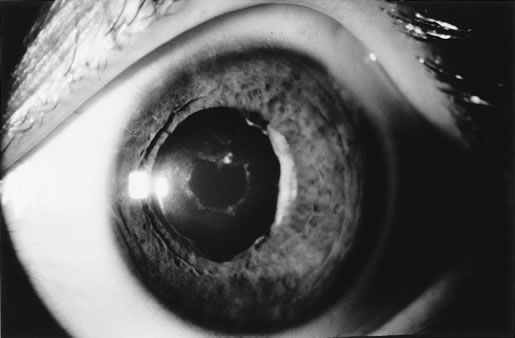

When phacoemulsification became available, it was quickly applied to the removal of children's cataracts because it provided the surgeon with better control of the flow of irrigating solutions and provided improved control of the aspiration flow and pressure.4 The instrument also added a new capability, that of being able to mechanically disrupt the lens nucleus and cortex to facilitate aspiration of the lens. Although the phacoemulsification instrument was helpful for removing lens cortex, it was ineffective in cutting or removing the posterior lens capsule. At the conclusion of the phacoemulsification procedure, the posterior capsule was left intact. When capsular opacification occurred, it was treated with a discission procedure, an operation that consisted of making a cut in the posterior capsule with a bent needle, a Ziegler knife, or a modification of the latter (Fig. 1). If the membrane was thick and resisted opening with a knife, an intraocular scissors was necessary to open the lens capsule.

The advantage of leaving the posterior capsule of the lens intact after cataract surgery is that it retains a barrier between the anterior chamber and vitreous. This prevents the vitreous from entering the anterior chamber, and it theoretically preserves the ocular anatomic relationships after cataract surgery. The disadvantage of leaving the posterior lens capsule intact is that when the capsule opacifies, a second procedure is needed to re-establish a clear visual axis. To achieve this, a second anesthetic is administered and an incision is made into the clear cornea. The chamber is deepened with a viscoelastic material and a knife or other instruments are introduced into the anterior chamber to cut or tear the posterior capsule so that the visual axis can be cleared (Fig. 1).